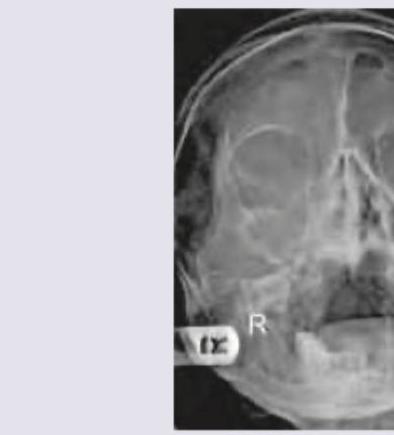

Explanation: ***Right sided pansinusitis*** - The image shows **opacification and mucosal thickening** in the **right maxillary, frontal, and ethmoid sinuses**, which is consistent with **pansinusitis**. - The sinuses on the left appear relatively clear compared to the complete opacification seen on the right side. *Fracture of mandible* - There is **no clear evidence of discontinuity or displacement** of the mandibular bone on the provided X-ray. - Mandibular fractures typically present as a **break in the cortical outlining** of the mandible, which is not visible here. *Orbital floor blowout* - An orbital floor blowout fracture would typically show **herniation of orbital contents** into the maxillary sinus, often accompanied by **air-fluid levels** or a **"teardrop" sign**, neither of which is clearly discernible. - While there is some soft tissue density in the right maxillary sinus, it's more representative of generalized inflammation rather than specific orbital contents. *Normal study* - The distinct **opacification of multiple sinuses** on the right side indicates an abnormality and is inconsistent with a normal study. - A normal sinus X-ray would show **clear, air-filled sinuses** with thin mucosal linings.